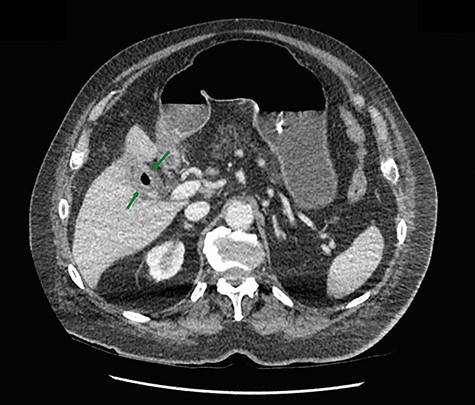

Given that the patient was clinically well, he was managed conservatively overnight with a nasogastric tube and intravenous fluid therapy. The CT scan was closely reviewed by the surgical team the following day and noted the presence of gas within the gallbladder, which was not commented upon by the radiologist (Fig. 2). Furthermore, SBO transition point appeared to be in the distal ileum, where a 3-cm “soft tissue” mass was seen (Fig. 3). His previous CT scan that diagnosed his chronic cholecystitis demonstrated a 3-cm gallstone within the gallbladder, which was not seen on the current CT. The findings of gas within the gallbladder in the setting of SBO and a mass of similar size to the known gallstone raised the suspicion for gallstone ileus. The patient then underwent a laparotomy and enterotomy for a 43-mm gallstone impacted in the distal ileum (Fig. 4). Apart from an episode of ileus, he made a full recovery post-operatively and was discharged home, with an outpatient follow-up in the surgical clinic.